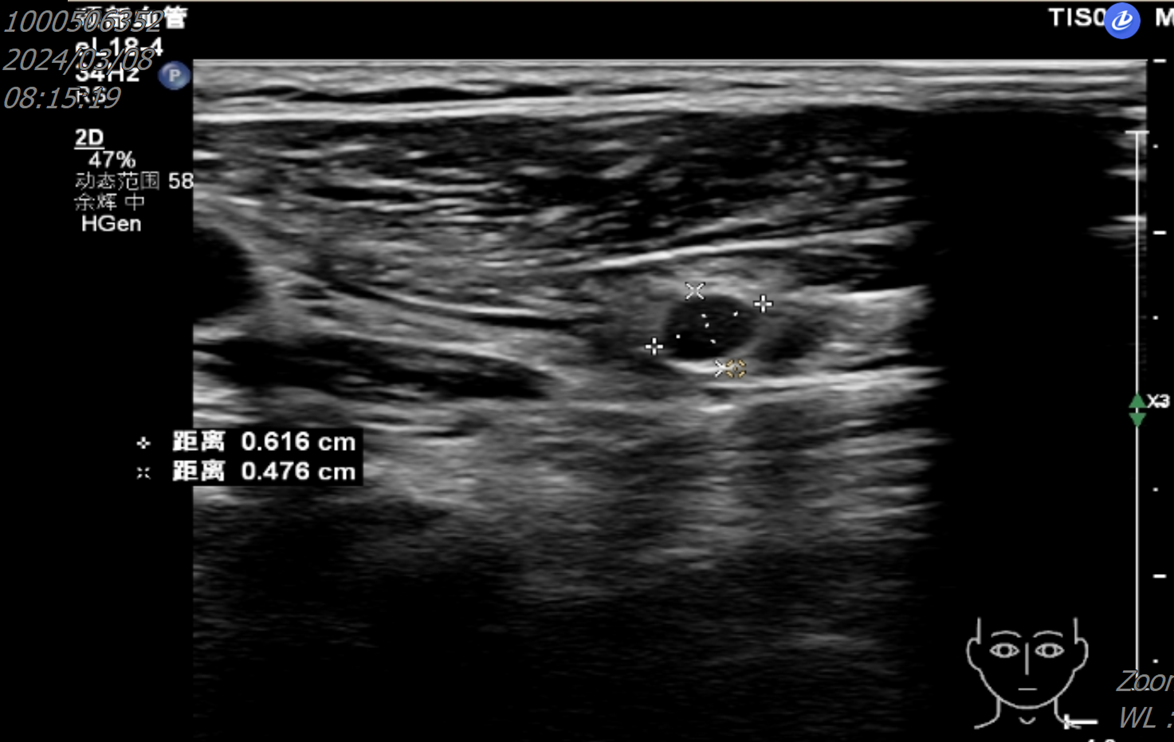

2024年4月至2025年7月,开始口服“长春瑞滨软胶囊 80mg D1/D8/D15,Q21D”。治疗期间复查胸部CT示,病灶较前明显缩小;颈部淋巴结超声示,颈部淋巴结较前缩小(图5);肿瘤指标下降。

图5 颈部超声(2025-06-19)

至2025年7月,患者已坚持治疗15个月,疗效评估:持续PR。